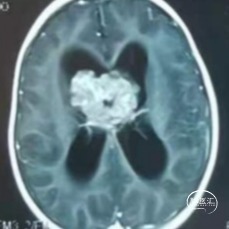

图1-a

术前头颅MRI提示,图1-a:T1增强扫描轴位,第三脑室肿瘤累及双侧侧脑室,右侧脑室内肿瘤体积较对侧大,幕上脑室扩张伴脑脊液外渗。